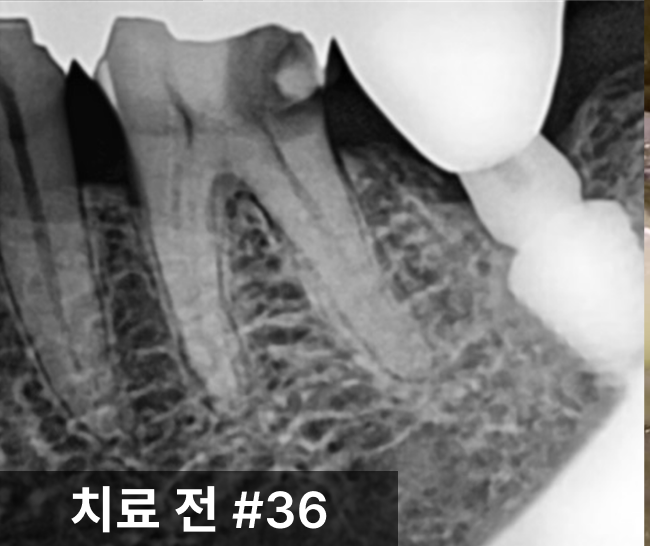

환자분의 왼쪽 아래 어금니(#36)는

기존 금 인레이 아래로 2차 충치가 발생한 상태였습니다.

통증이 동반되었으며, 충치 깊이가 신경에 도달해

신경치료가 불가피한 상황이었습니다.

신경치료를 통해 염증 부위를 제거하고,

레진으로 내부를 밀봉한 뒤 크라운을 수복했습니다.

치근까지 염증이 진행되기 전 내원하신 덕분에

발치 없이 치아를 보존할 수 있었습니다.

조기 내원의 중요성이 잘 드러난 케이스입니다.